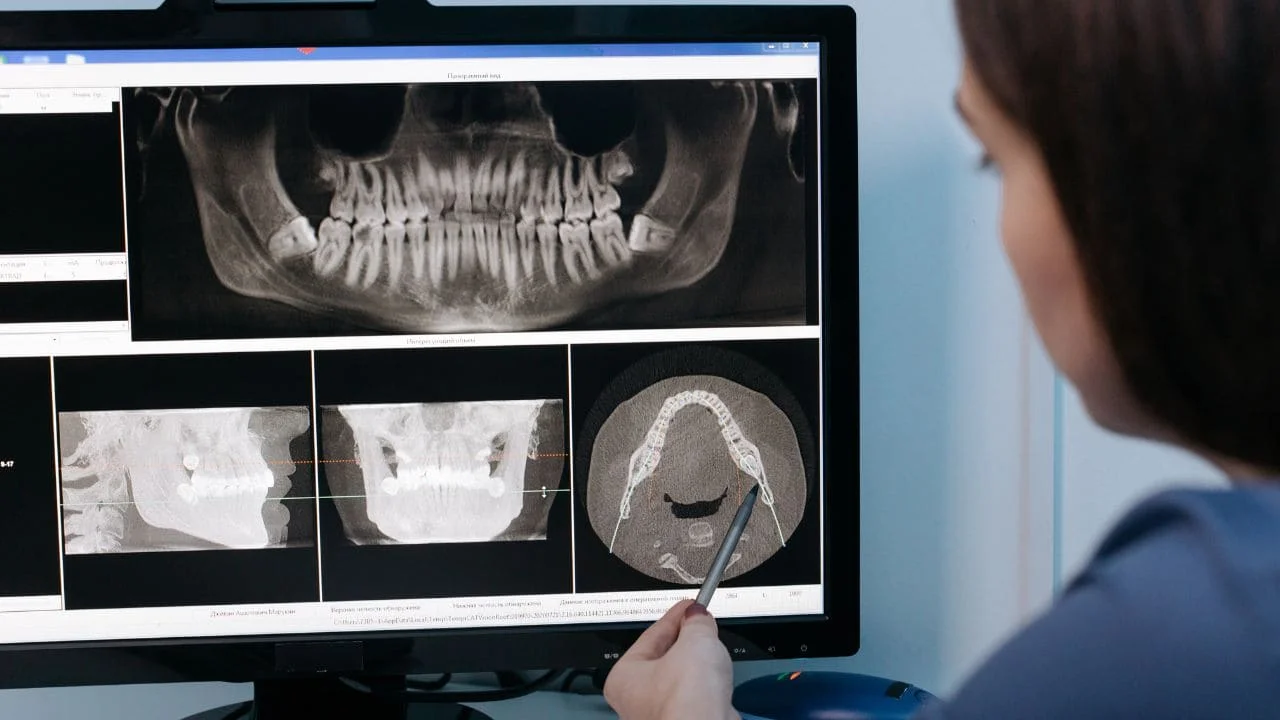

Un dentiste pour enfant, également appelé pédodontiste, est un professionnel spécialisé dans les soins dentaires des plus jeunes, de la naissance jusqu’à l’adolescence. Contrairement à un dentiste généraliste, le pédodontiste suit une formation supplémentaire de 2 à 3 ans axée sur la psychologie infantile, la croissance des mâchoires, et les techniques de soins adaptées aux enfants.

- Radiographies si besoin (environ une fois par an)